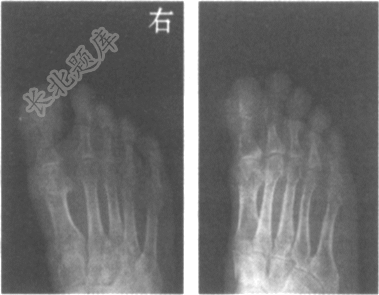

- [材料题] 男,75岁,右足第1跖趾关节和

趾趾间关节疼痛3天,局部红肿,每于夜间痛醒,半年前有类似发作史。

- 多项选择题1.结合右足正斜位片,最可能的诊断是

- C